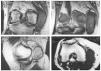

En la resonancia nuclear magnética (RNM) se aprecia (fig. 2): discreto derrame articular; disminución del cartílago articular, sugerente de una condromalacia patelar o el comienzo de una osteoartritis degenerativa; lesión meniscal grado II del cuerno posterior del menisco interno y una imagen tumoral de aproximadamente 7 x 7 x 3 cm de tamaño, de contorno bien definido, de aspecto quístico, polilobulada, septada en su interior y localizada junto al LLI y los músculos sartorio y recto interno que bien pudiera ser una bursitis de la pata de ganso, un ganglión quístico o un hematoma.

Fig. 2.—RNM donde se aprecia tumoración en la zona posterointerna de la rodilla. / Fig. 2.—NMR showing a tumour in the posterointernal area of the knee.